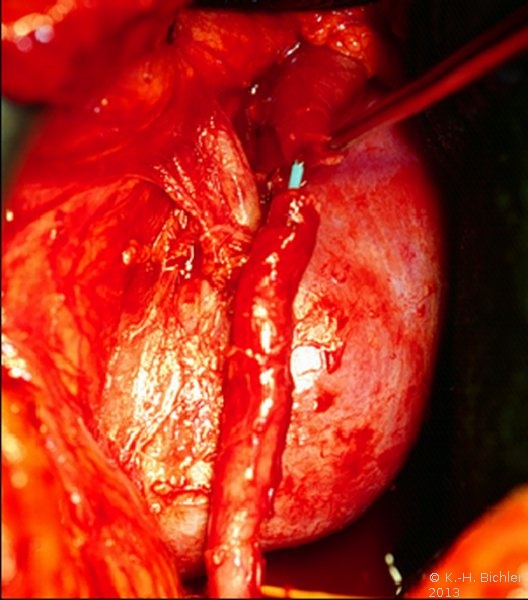

Die Nierenfreilegung ergab ein aberrierendes Gefäß. Die Abbildung zeigt schematisch das strangulierende Gefäß und das gestaute Nierenbecken (Abbildung 8).

Bei der operativen Korrektur wurde der Harnleiter durchtrennt und vor dem Gefäß End-zu-End-anastomosiert (Abbildung 9).